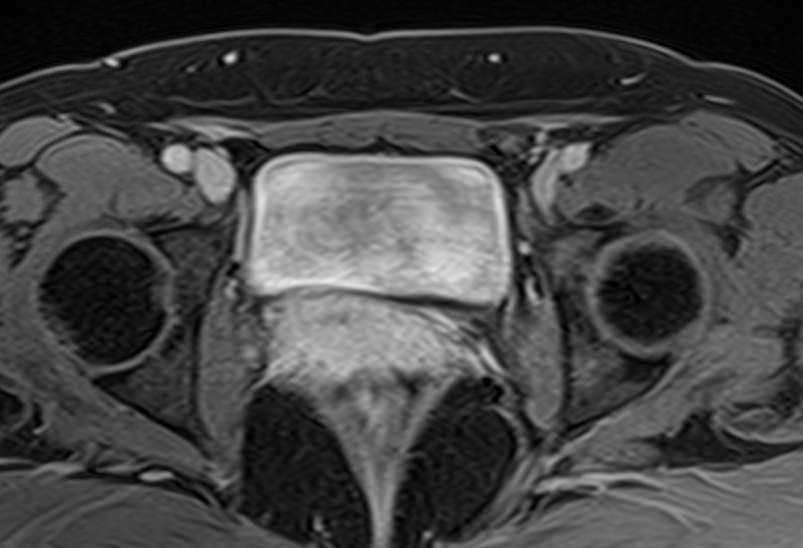

МРТ мочевого пузыря позволяет найти причины возникновения вышеперечисленных симптомов, выявить патологические изменения в мочевом пузыре, окружающих органах и тканях, поставить точный и достоверный диагноз. Процедура безболезненна и при отсутствии противопоказаний безопасна. Метод МРТ не предусматривает использование вредного рентгеновского излучения, поэтому может проводиться неоднократно в течение короткого периода времени, что, например, бывает важно для оценки эффективности лечения.

Но несмотря на высокую диагностическую ценность магнитно-резонансной томографии, в некоторых случаях для улучшения визуализации патологических очагов дополнительно применяется контрастное усиление. В частности, при подозрении на опухолевые образования мочевого пузыря (как первичные, так и метастатического происхождения) требуется внутривенное введение контраста.

Проведение МРТ с контрастированием, в первую очередь, применяется в онкодиагностике. Метод позволяет детально визуализировать опухоль, ее локализацию, размеры, степень прорастания в окружающие ткани, оценить стадию развития. Кроме того, МРТ незаменима в сложных диагностических случаях, при получении неоднозначных противоречивых данных предыдущих обследований.